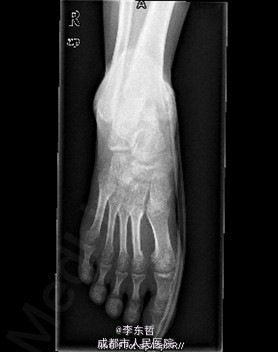

患者女,13岁4月,因“车祸致右足跟部皮肤撕脱伤清创缝合术后25天”入院。患者25天前因车祸导致右足疼痛流血伴功能障碍,右足跟部皮肤撕脱,遂到当地医院就诊,诊断为右足跟部皮肤严重剥脱伤,右跟骨骨折,右胫骨远端骨折。急诊下行“右足跟部皮肤严重剥脱伤清创缝合术”。术后给予止痛、消肿、预防感染等对症处理,目前右足外侧及跟部皮肤变暗,坏死。患者为进一步诊疗,故请我院远程会诊后转入我科继续治疗。患者病来精神、饮食可,大小便正常,体重未见明显改变。

查体:右足内踝、外踝及跟部皮肤变暗,部分缺血坏死。未见畸形,稍肿胀。触:右足趾皮温无明显降低,右足趾感觉未见明显异常。右足内踝、外踝及跟部皮肤局部压痛。动量:右踝关节活动受限,右踝关节活动诱发疼痛。右膝关节活动未见明显异常。 辅助检查:X线示:右跟骨骨折,右胫骨远端骨折。

初步诊断:1、右足跟部皮肤软组织撕脱伤清创缝合术后皮肤软组织大面积坏死伴感染;2、右跟骨骨折;3、右胫骨远端骨折;4、右足跖屈畸形。 处理:1、向患者及家属交待病情及注意事项。2、向上级医生汇报患者病情。3、完善相关术前等检查,择期行手术治疗。4、给予对症支持治疗。5、密切观察病情变化,根据病情及时处理。